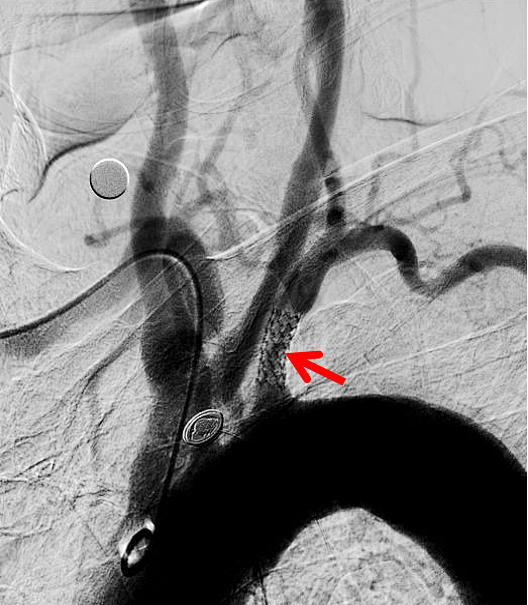

术前左侧锁骨下起始段重度狭窄

术后狭窄解除,血管恢复正常形态